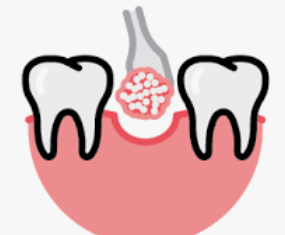

임플란트 뼈이식 후 치유 과정에는 골융합이라는 과정에서 기존 뼈와 통합되는 새로운 뼈 재료가 포함됩니다. 이것은 이식된 뼈의 양과 개인의 치유 능력에 따라 몇 달이 걸릴 수 있습니다.

8. 치과 임플란트 식립

임플란트 뼈이식으로 뼈재생이 충분히 이루어졌음을 치과의사가 방사선 사진을 통해 확인하면 임플란트 식립을 진행할 수 있습니다.